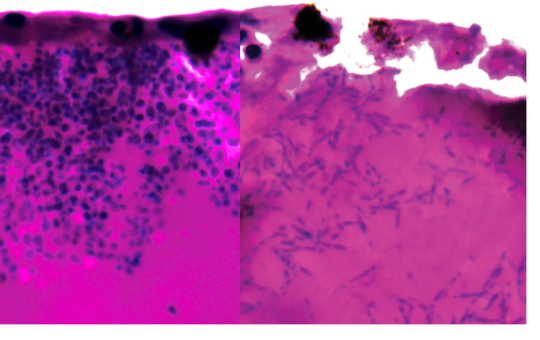

Twenty-four clinicians and laboratory technicians have enrolled in a bespoke training programme designed to strengthen the diagnosis and treatment of deadly fungal...